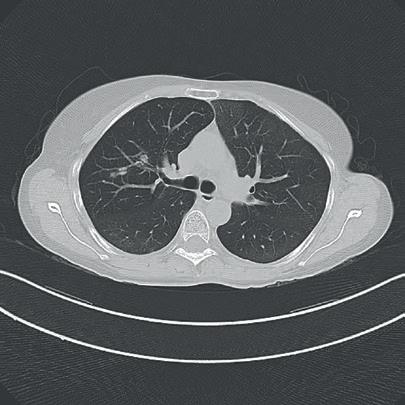

The incidence of lung cancer has increased considerably in the last few decades with the lung as the most common site of metastatic involvement. Despite the improvements in the diagnosis and treatment for malignant lung tumours, the prognosis of the patients is still unsatisfactory.1 Currently, locoregional chemotherapeutic techniques such as transpulmonary chemoembolization (TPCE) for the treatment of lung malignancies have gained increasing importance. The purpose of this retrospective study was to evaluate local tumour response and patient survival after the treatment of pulmonary metastases using TPCE as a palliative treatment method.

In TPCE, a 5 French (Fr) endovascular sheath and 5Fr headhunter catheter are routinely placed transfemorally under fluoroscopy until the pulmonary artery and subsequently the tumourfeeding segmental pulmonary branch are reached. A balloon catheter (up to 7mm in diameter) is optionally placed for better results.2 This selective pulmonary artery catheterisation results in a blockage of the arterial supply to the tumour tissue, resulting in regional ischaemic necrosis in the target tumour tissues while reducing damage to the surrounding normal lung parenchyma. Thereafter, mitomycin

and gemcitabine as chemotherapeutic agents are administered in combination with an embolization of lipiodol and microspheres. This extends the storage time of the injected cytostatics in the tumours and reduces the outflow into

the circulatory system.3 Consequently, the frequency and severity of systemic effects are limited. Other occlusion materials used are coils, polyvinyl alcohol, degradable starch microspheres, and gelatin sponges.

In our study, 223 patients (138 women, 85 men; mean age: 59.3±11.9 years) with unresectable lung metastases and/or not responding to systemic chemotherapy received repetitive TPCE (mean number of sessions 4.7±3.7) between January 1990 and May 2021. Patients had predominant lung metastases and in most cases with bilateral lung involvement. Origin of the metastases were either colorectal carcinoma (n=139) or breast cancer (n=84). Tumour-supplying vessels were catheterised selectively in order to apply chemotherapeutic agents locally, combined with lipiodol and microspheres. The response was assessed according to the revised RECIST criteria.

Of the evaluated 183 cases, partial response was achieved in 4.9% (n=9), stable disease in 62.3% (n=114), and progressive disease in 32.8% (n=60) of the patients. Mean and median overall survival time were 23.5 and 14 months, respectively.

TPCE can be used as a palliative treatment in unresectable lung malignancies to reduce the tumour burden or to achieve local tumour control,4 or as a neoadjuvant or curative treatment option combined with thermal ablation such as radiofrequency ablation (RFA) and microwave ablation (MWA) (Figure 1).5,6

A multicentre study may include a larger population of patients and combine expertise from different institutes. Although TPCE has the potential to improve local tumour control and to prolong survival, randomised controlled trials are still needed.